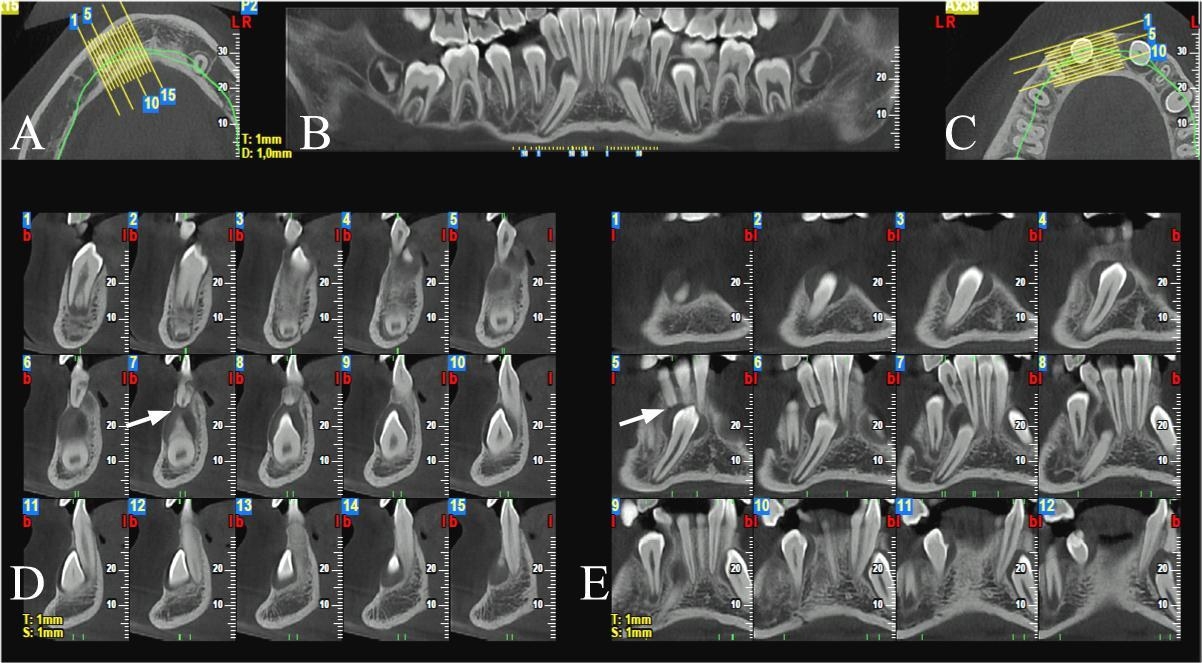

Sezioni Tomografiche (TC/Tac) e Ricostruzioni 3D dei mascellari Ortopantomografia delle arcate dentarie a bassa emissione di radiazioni X Ortopantomografia delle arcate specifica per uso pediatrico Rx Stratigrafia dei condili mandibolari compresa ATM Emimandibola dx/sx Adatta per adulti e bambini, veloce e indolore, consente di ottenere in tempo reale i referti necessari per le diagnosi e la pianificazione delle cure. Lo specialista garantisce le stesse tariffe applicate presso le strutture sanitarie specializzate esterne pur offrendo un prodotto avanzato, confortevole e sicuro.